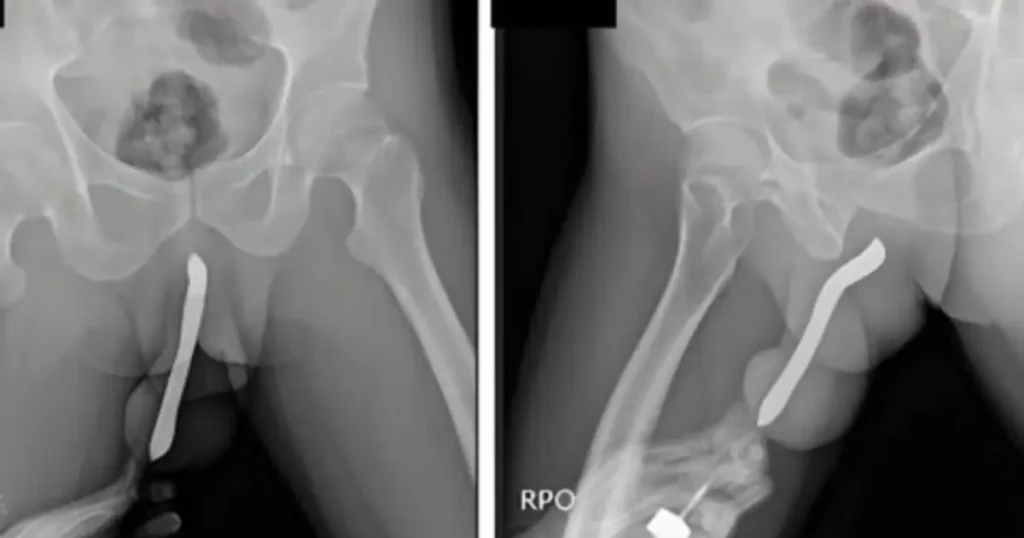

Dados dos EUA mostram os objetos mais inseridos nos órgãos sexuais masculino e feminino; confira a lista

Um grande número de pessoas procura prontos-socorros todos os anos após introduzir objetos nos órgãos genitais. A partir desse cenário, o site norte-americano Defector analisou dados recentes da Comissão de Segurança de Produtos de Consumo dos Estados Unidos (CPSC), que reúne registros de atendimentos de emergência e os motivos que levam pacientes ao hospital. […]